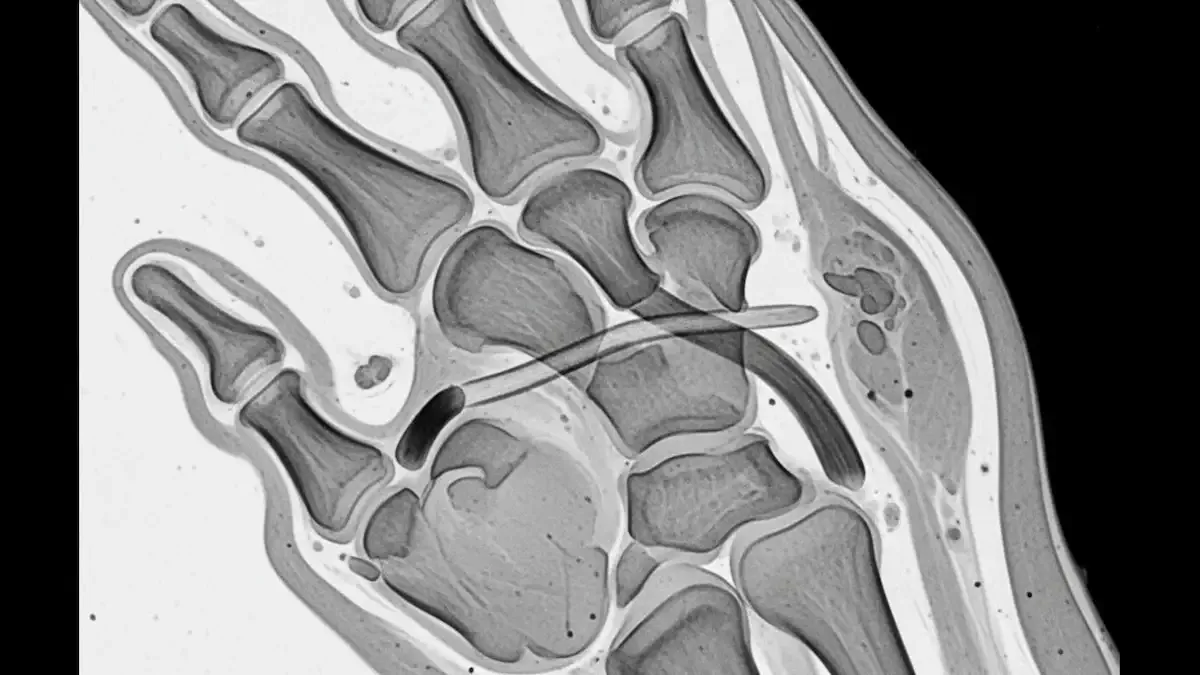

Os dedos têm ligamentos colaterais dos dois lados de cada articulação. No polegar, o ligamento colateral ulnar fica no lado “interno” da articulação metacarpofalangeana, perto da comissura entre o polegar e o indicador.

Ele funciona como uma corda de contenção lateral, mantendo a articulação estável quando você faz força de pinça ou segura objetos.

Quando esse ligamento rompe, o polegar pode “abrir” para o lado e perder estabilidade.

O detalhe que define a lesão de Stener é a interposição do tecido do adutor do polegar, que impede o retorno do ligamento à posição correta.

A radiografia não “mostra” o ligamento, mas é útil para procurar fraturas associadas, principalmente fratura por avulsão na base da falange.

Já o ultrassom e a ressonância magnética conseguem avaliar o ligamento e podem identificar se existe deslocamento compatível com lesão de Stener.

A ressonância costuma dar uma visão mais completa, com maior custo e, às vezes, mais demora para agendar.